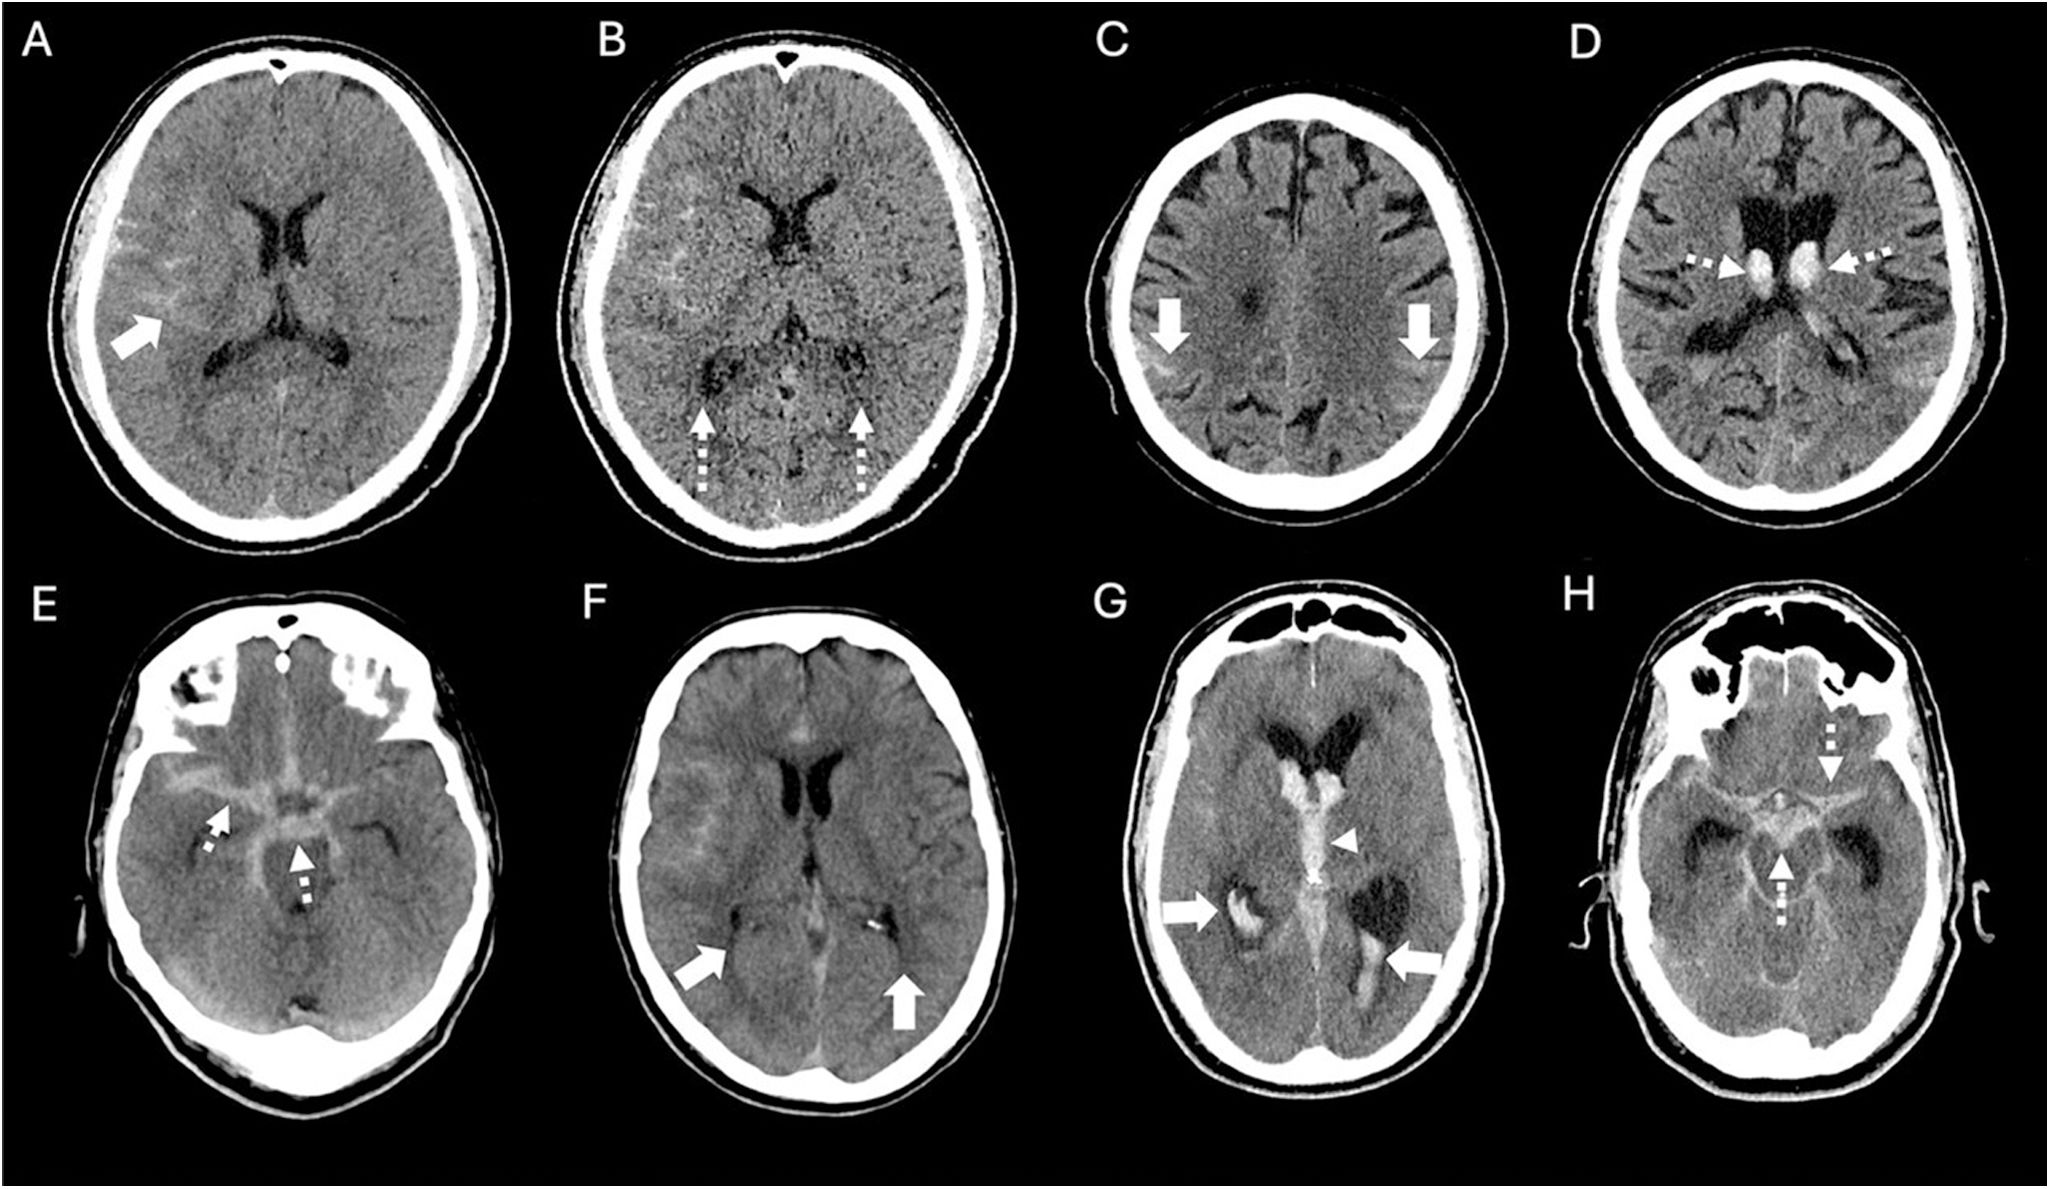

La hemorragia subaracnoidea espontánea (HSA) es una urgencia neurológica que afecta predominantemente a adultos jóvenes, con una elevada tasa de mortalidad y secuelas neurológicas graves en los supervivientes. Su manifestación clínica más característica es la cefalea súbita en trueno, considerada la peor cefalea de la vida, frecuentemente acompañada de alteraciones del nivel de conciencia y rigidez de nuca. La tomografía computarizada craneal sin contraste (TCCSC) constituye la herramienta diagnóstica inicial de elección, con alta sensibilidad. El reconocimiento de patrones de distribución del sangrado en la TCCSC permite orientar el diagnóstico etiológico y valorar la presencia de complicaciones como hidrocefalia, hemorragia intraventricular o edema cerebral. Esta primera parte del artículo proporciona una guía práctica y detallada basada en la imagen para el radiólogo en la fase hiperaguda de la HSA espontánea, diferenciando entre patrones aneurismáticos, perimesencefálicos y corticales, y discutiendo sus implicaciones clínicas, diagnósticas y terapéuticas.

Spontaneous subarachnoid haemorrhage (SAH) is a neurological emergency that predominantly affects young adults, with a high mortality rate and severe neurological sequelae in survivors. Its most characteristic clinical manifestation is a sudden thunderclap headache, often described as the worst headache of one's life, and frequently accompanied by altered levels of consciousness and neck stiffness. Non-contrast cranial computed tomography (NCCT) is the initial diagnostic tool of choice due to its high sensitivity. Recognising the distribution patterns of haemorrhage on NCCT helps guide the aetiological diagnosis and assess the presence of complications such as hydrocephalus, intraventricular haemorrhage or cerebral oedema. This article offers a practical and detailed imaging-based guide for radiologists in the hyperacute phase of spontaneous SAH, distinguishing between aneurysmal, perimesencephalic and cortical patterns, and discusses their clinical, diagnostic and therapeutic implications.